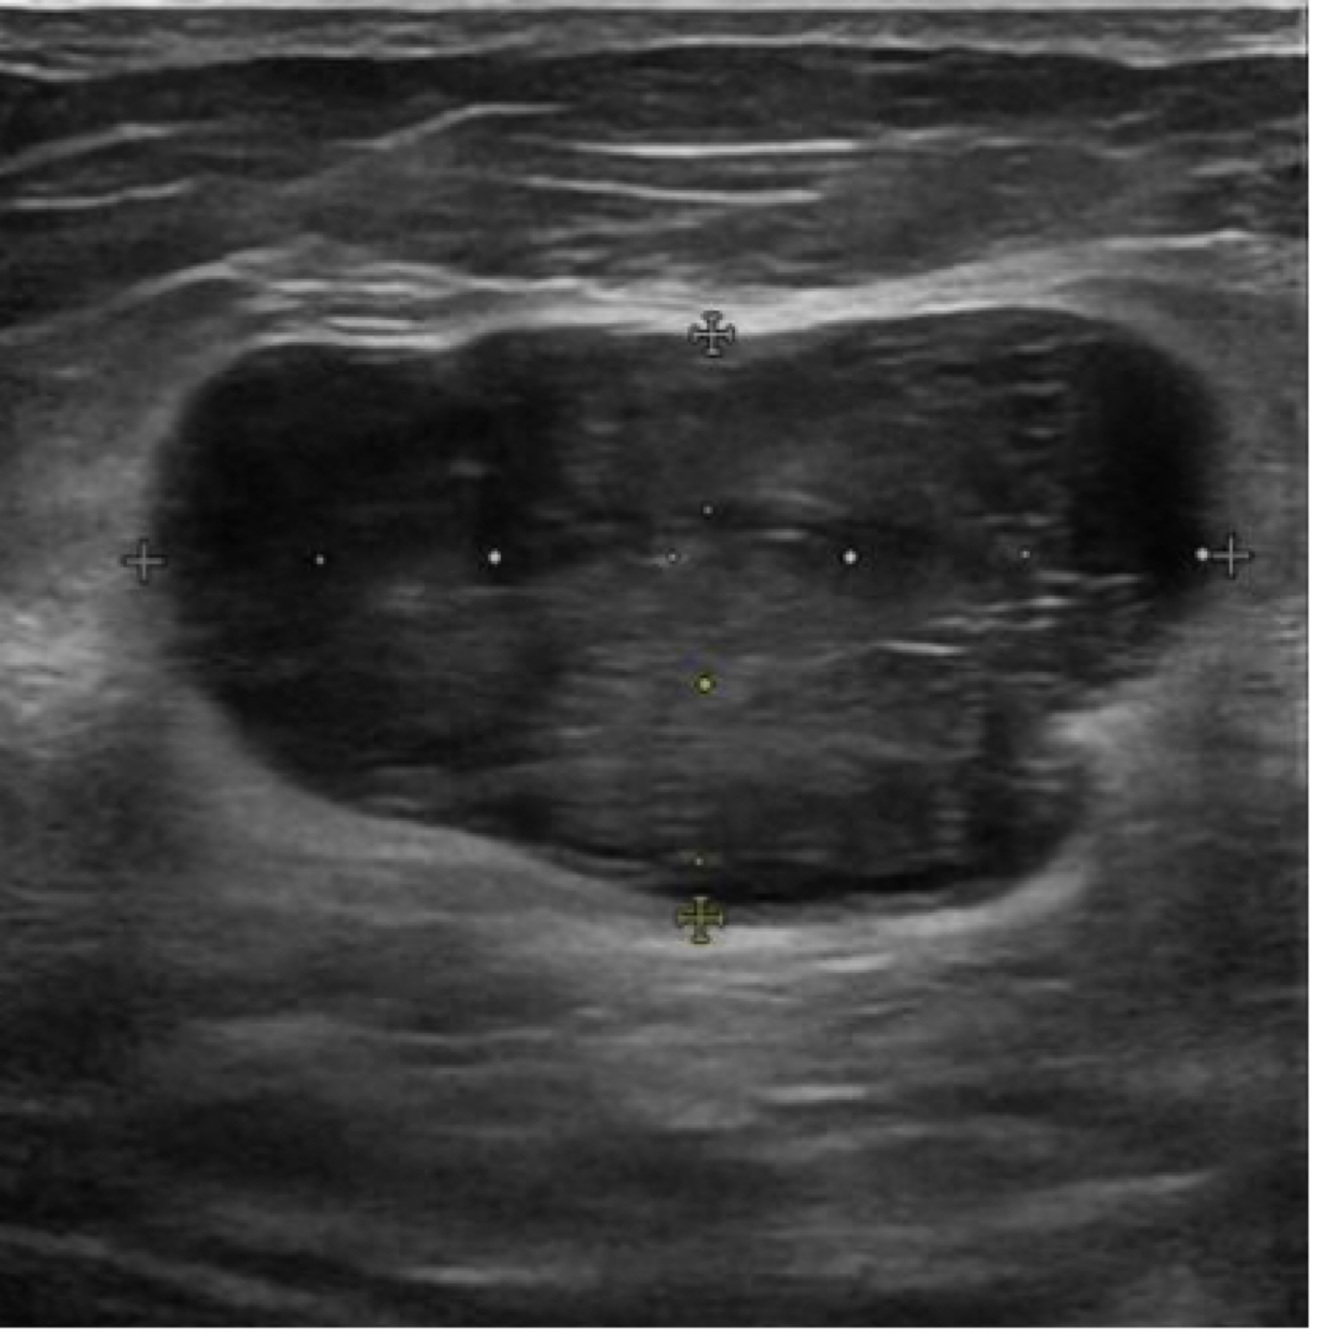

What kind of cyst is this?

Simple cyst (breast in this image)